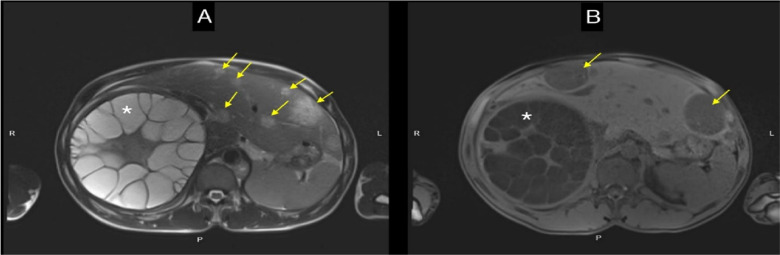

From a global perspective, hepatocellular carcinoma (HCC) and hydatid cyst disease are both common; however, the endemic and zoonotic nature of hydatid cysts (due to Echinococcus larvae) makes the simultaneous detection of the two conditions a rare occurrence. In this case report, in a 43-year-old male patient, we aim to draw attention to the potential coexistence of HCC and liver hydatid cysts by presenting a case in which HCC tissue was detected in the cyst wall-removed by emergency surgery due to cyst perforation. Hydatid lesions in the liver may exhibit tumor-like growth characteristics. Consequently, identifying a hydatid cyst concomitant with HCC can be challenging, particularly when HCC has developed within the cystic structure. Careful assessment of resected tissues and detailed diagnostic approaches can facilitate the identification of such cases, even if the risk of HCC in patients with hydatid cysts is marginal. It may be advisable to suggest periodic monitoring with HCC-related markers and liver imaging methods.